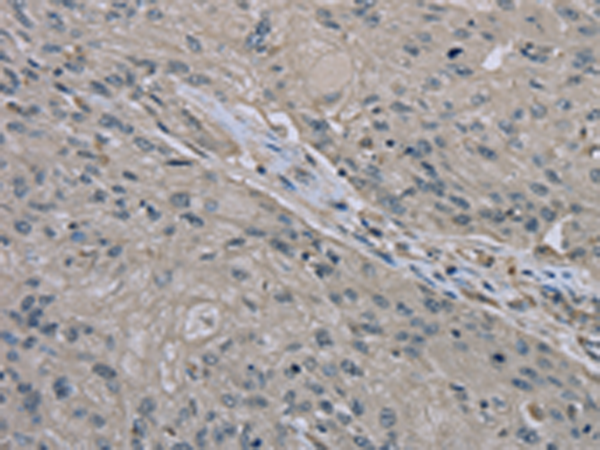

分类: 科研抗体货号: P08296别名: HSCO; YF13H12应用: WB,IHC反应种属: Human, Mouse